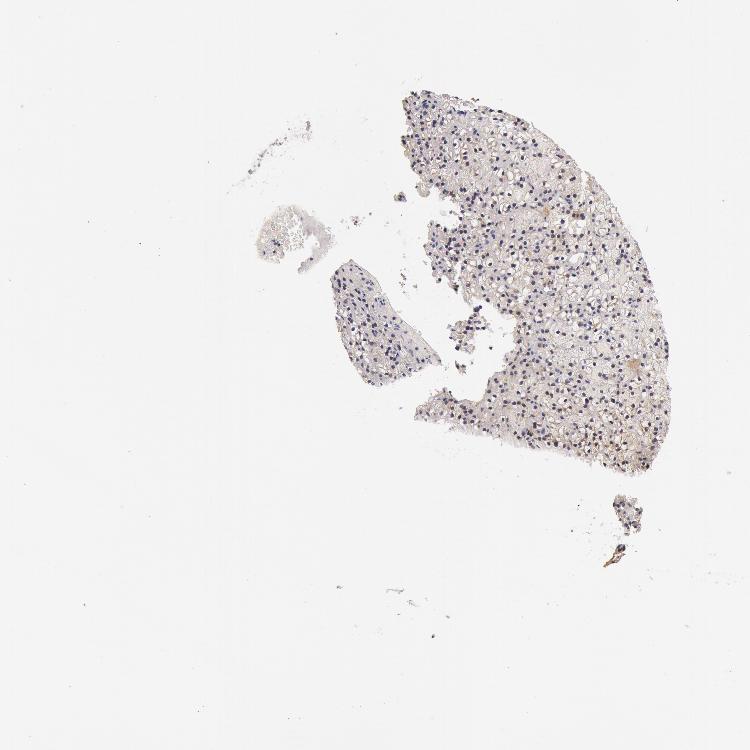

PARATHYROID GLAND - Antibody stainingi

Antibody staining in the annotated cell types in the current human tissue is reported as not detected, low, medium, or high, based on conventional immunohistochemistry profiling in selected tissues. This score is based on the combination of the staining intensity and fraction of stained cells.

Each image is clickable and will lead to virtual microscopy that enables deeper exploration of all samples and also displays staining intensity scores, fraction scores and subcellular localization as well as patient and tissue information for each sample.

Antibody HPA001589

Glandular cells Not detected